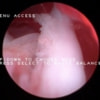

関節穿刺を行い、好中球はなく、少数のマクロファージや滑膜細胞が認められるました。膝蓋骨脱臼および前十字靭帯断裂による退行性の関節炎を疑い、関節鏡検査を実施いたしました。関節鏡検査では、重度の滑膜炎および前十字靭帯の完全断裂が認められました。内外側とも半月板に損傷は認められませんでした。

断裂前十字靭帯の除去を行いました。外側方向からのテンションが著しく、外側広筋と膝関節外側支帯の解放を行いました。膝関節伸展機構の著しいアライメント異常が認められたため、脛骨粗面転移術を実施しました。

写真の膝関節の垂直線を綿棒の木柄が表しており、遠位の脛骨粗面との位置関係が平行ではありません。